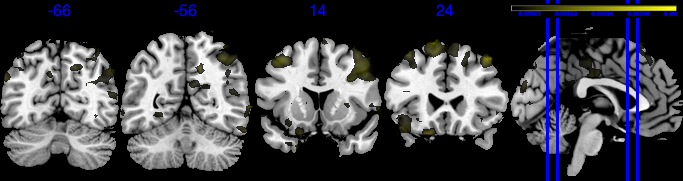

We performed 100,000 iterations for the outcome model (1), discarding the first 50% as burn-in and thinning to retain 1,000 posterior samples. For the mediator model (2), we ran 40,000 iterations with a 30,000 burn-in, thinning every 10 iterations to obtain 1,000 posterior samples. Table 3 gives a summary of both the overall NIE and NDE and the top seven regions identified with the largest number of active voxels. The definition of NIE in each region is , where is the collection of all voxels in region . The rule for selecting the active voxels is based on cutting the posterior inclusion probability (PIP) at 50%, and the three regions with active voxels are reported in Table 3. Due to the very small effect sizes and low signal-to-noise ratio, we also include regions with voxels’ PIP greater than 10%. The posterior of NDE has a mean of 0.27 with the 95% credible interval . The posterior of NIE has a mean of 0.0885 with the 95% credible interval . The total effect of parental education level on general cognitive ability score is 0.36, with 95% credible interval (0.29,0.45). This suggests that parents with college degrees have a positive impact on children’s cognitive abilities, and about 25% of the effect is mediated through brain cognitive development. Figure 5 shows the estimated activation regions and the NIE in coronal view slides. Among the top identified activation regions, the most interesting is the left precuneus, which plays a key role in episodic memory, visuospatial processing, and self-consciousness (lou2004parietal; wallentin2006parallel). This region has been consistently implicated in cognitive processes related to memory retrieval and spatial awareness, which are crucial components of children’s cognitive development. In addition, other identified regions, such as the left inferior parietal region and the left postcentral gyrus, are associated with the interpretation of sensory information (radua2010neural; diguiseppi2023neuroanatomy). These regions are involved in integrating and processing sensory inputs, which are essential for tasks that require coordination between perception and cognition, such as working memory and executive function. These findings align with existing literature on the neural correlates of cognitive function, particularly in children. By identifying regions that have been consistently associated with cognitive processes, our results not only demonstrate the scientific validity of the BIMA approach but also provide meaningful insights into the brain areas that underlie cognitive abilities as captured by the ABCD study.

| Posterior inclusion probability (color range ) |

![]() |

| Positive posterior mean of the spatial mediation effects (color range ) |

| Negative posterior mean of the spatial mediation effects (color range ) |